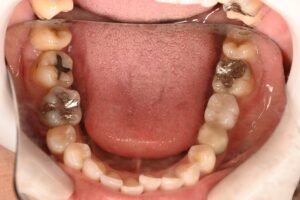

今回は奥歯を1本抜歯後にインプラントを選択された患者様のケースです。

左下の奥歯の痛みで来院されました。

口腔内とレントゲン撮影によって診査していきます。